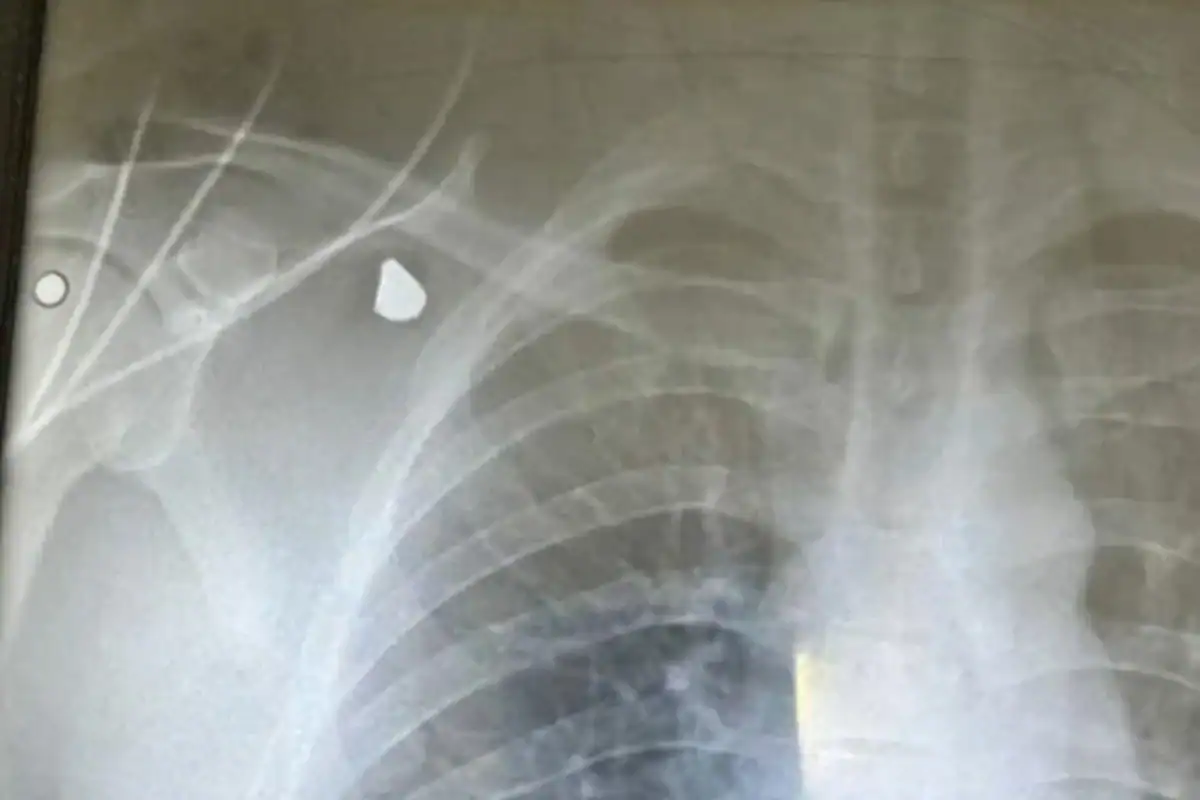

“Eduardo Moura, isso aqui é um tiro, entendeu? Eu fui baleado, passou quase próximo ao meu pulmão. Eu nunca ia brincar com uma situação dessa e você fazendo vídeo pra se autopromover”, começou.

“NASCI DE NOVO”, AFIRMOU. Em seguida, ele continuou relatando: “Eu sou um ser humano, além de ser um cantor (entre aspas) como você fala. Eu tenho mãe, tenho família e tava trabalhando, é o meu trabalho. Isso aqui eu fui alvejado, eu nasci de novo. Isso aqui é um tiro”, mostrou.